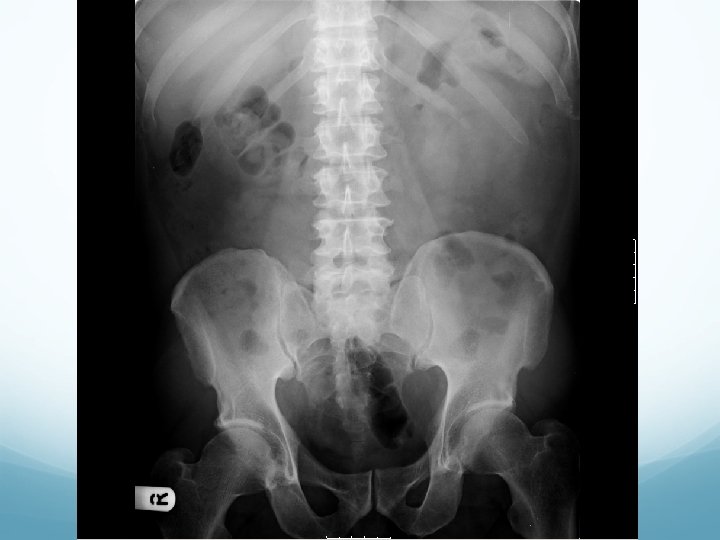

What to look for on a KUB � 90% stones are radio-opaque � Ureteric stones are sausage shaped due to peristalsis of ureters 1. Outline of kidneys 2. Path of ureters � Hila of kidneys L 1 � Tips of transverse processes � SIJ at pelvis 3. Sites of impaction � PUJ � Pelvic Brim � VUJ 4. Rest of abdominal film

1. Outline of kidneys 1. Path of ureters 1. Sites of impaction 1. Rest of abdominal film

What to look for on an IVU � ALWAYS look at KUB first � CT KUB is gold standard, and only option if U+Es are abnormal 1. Nephrogram � � Contrast in kidney Persistent increasingly dense nephrogram in obstruction 2. Pyelogram � Calyces: � � � ? clubbed / more prominent Extravasation of contrast Ureters: � � � Peristalsis: Normal Dilatation Standing column